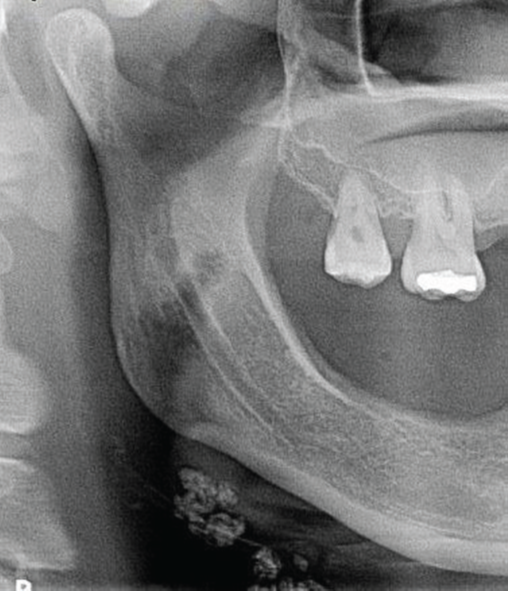

1) Identify the asymptomatic radiopacity indicated by the arrows. Patient was 65 years old and suffered from Diabetes and hypertension.